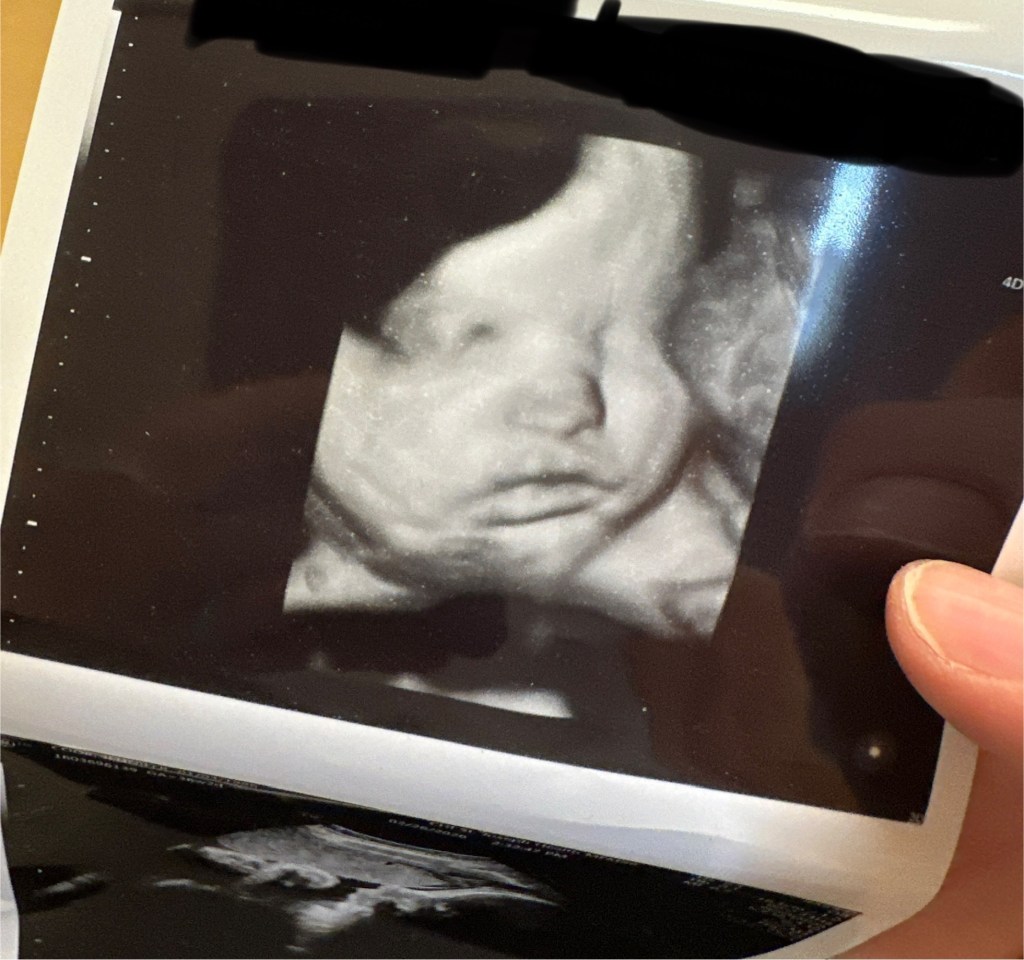

But here I am. 9 months pregnant now, Less than four weeks from my due date which probably means 3 weeks from having a baby because the doc(s) are pretty adamant I deliver before my due date because I’m 40.

We are getting so anxious to meet our sweet boy.